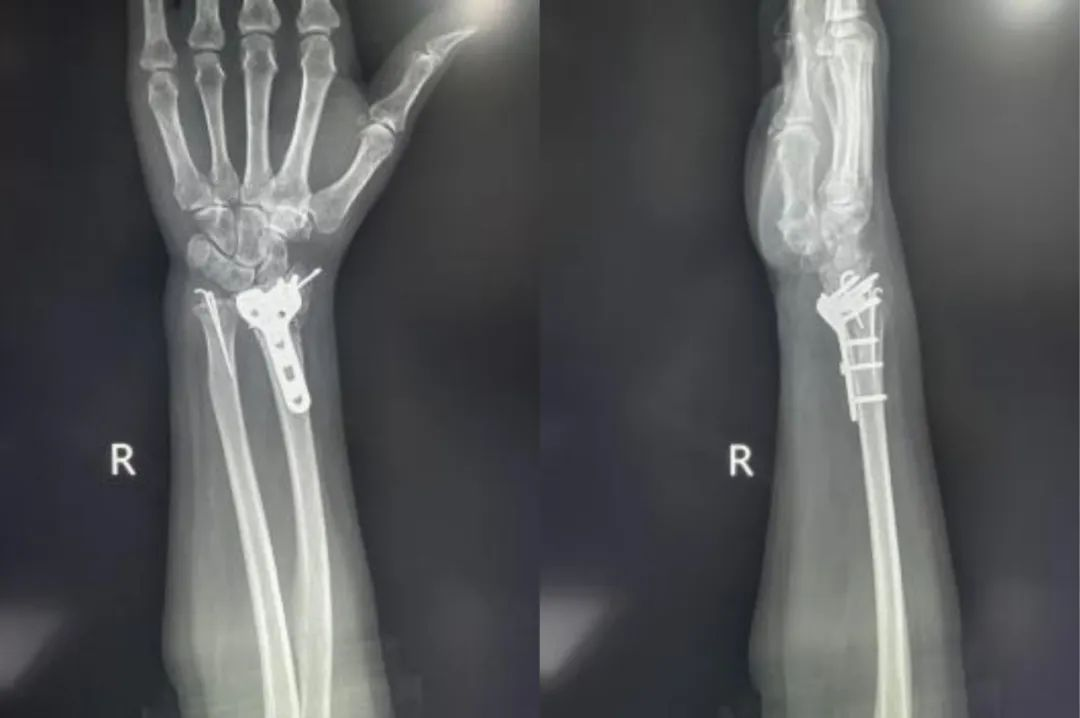

Primer ①